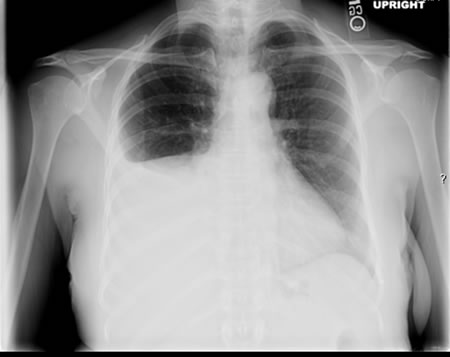

[Figure caption and citation for the preceding image starts]: Right-sided pleural effusionFrom the personal collection of David Horne and Masahiro Narita; used with permission [Citation ends].